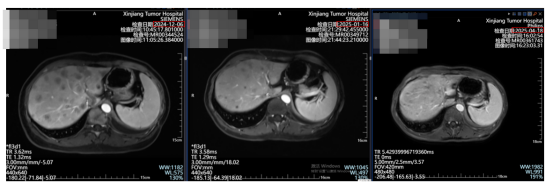

没想到,芦康沙妥珠单抗真的对我很有效!才用了一个月,肝脏上密密麻麻的病灶就明显缩小;到第四个月复查,磁共振上只剩黄豆大小的残留。

图为:芦康沙妥珠单抗治疗前后肝脏病灶的变化